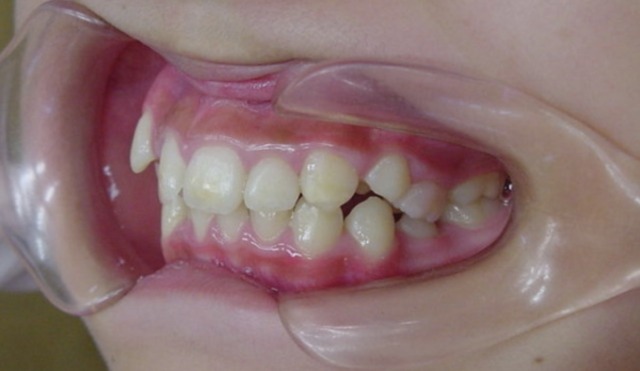

Before